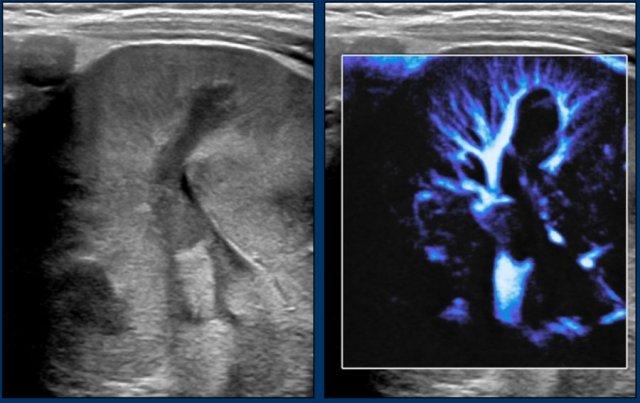

Hình ảnh

Nephroblastomatosis dai dẳng ở một bé trai bảy tuổi đã được điều trị u Wilms cách đây năm năm. Quan sát thấy một viền mô tăng hồi âm ở ngoại vi. Các tổn thương tồn dư này được theo dõi bằng siêu âm định kỳ cho đến năm năm sau điều trị.

Kỹ thuật hình ảnh vi dòng chảy (microflow imaging) có thể hỗ trợ xác định các vùng giảm tưới máu trong nephroblastomatosis.

Bé trai hai tuổi có u Wilms ở thận trái và nephroblastomatosis hai bên. Trên hình ảnh màu vi dòng chảy, vùng tổn thương có tưới máu kém hơn so với mô thận bình thường.